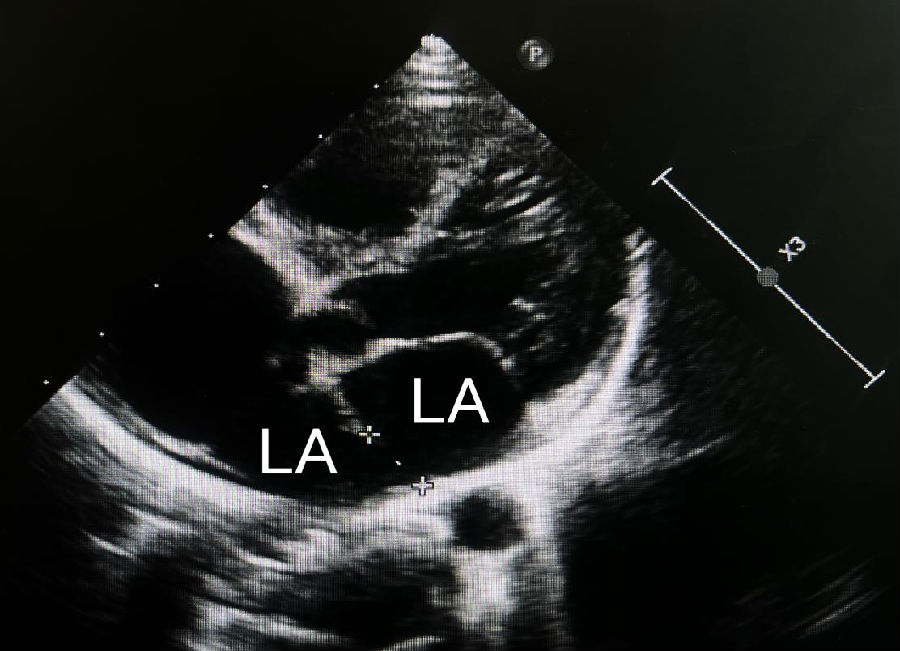

三房心是一种罕见的先天性心脏异常,于1868年被首次描述,仅占所有先天性心脏畸形的0.1%至0.4%,大多数患者在婴儿期或儿童期即被诊断出,成人的病例很少,可以涉及左心房或右心房,其定义为心房(左或右)内的异常隔膜,导致向各自的心室流入阻塞,它更常见于左心房。它要么以孤立的经典形式存在,要么可能与简单或复杂的先天性心脏异常有关。男性和女性之间没有发现该疾病发病率有明显差异,文献中也没有描述相关的遗传疾病。在高达80%的儿科人群中,该异常可能与其他先天性心脏病变有关,最常见的是房间隔缺损和肺静脉异位引流。

在体检中,有时可以通过听诊检测到心脏杂音。杂音的强度取决于血流通过隔膜的速度。超声心动图(经胸或经食道)是评估三房心解剖学和生理学的主要成像方式,彩色多普勒下的花色血流信号通常表示血流的加速和湍流的出现,这表明可以通过血流通过隔膜时可能有梗阻。经食管超声心动图的成像优于经胸超声心动图,可以明确的诊断三房心,并区分真正的左心房、左心房附属物以及隔膜的形态和梗阻程度。三维超声心动图是一种新的诊断工具,可以给临床提供额外的信息,能够明确隔膜的大小、位置和开口数量等。